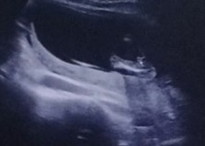

แบบนี้ใช่ผู้ชายไหมค่ะ ใช่จู๋น้องหรือเปล่า

หมอบอกผู้ชาย 90% เดือนหน้าจะฟันธงอีกทีค่ะ

ถ้าหมอบอก 90% เชื่อได้เลย ส่วนใหญ่จะไม่พลาด